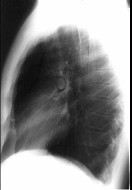

在哮喘急性发作的病程中患者出现颈部皮下气肿,胸片见图。说明此患者有下列哪一种并发症存在 ( ) HX-05051.jpg HX-05052.jpg

• A.纵隔气肿